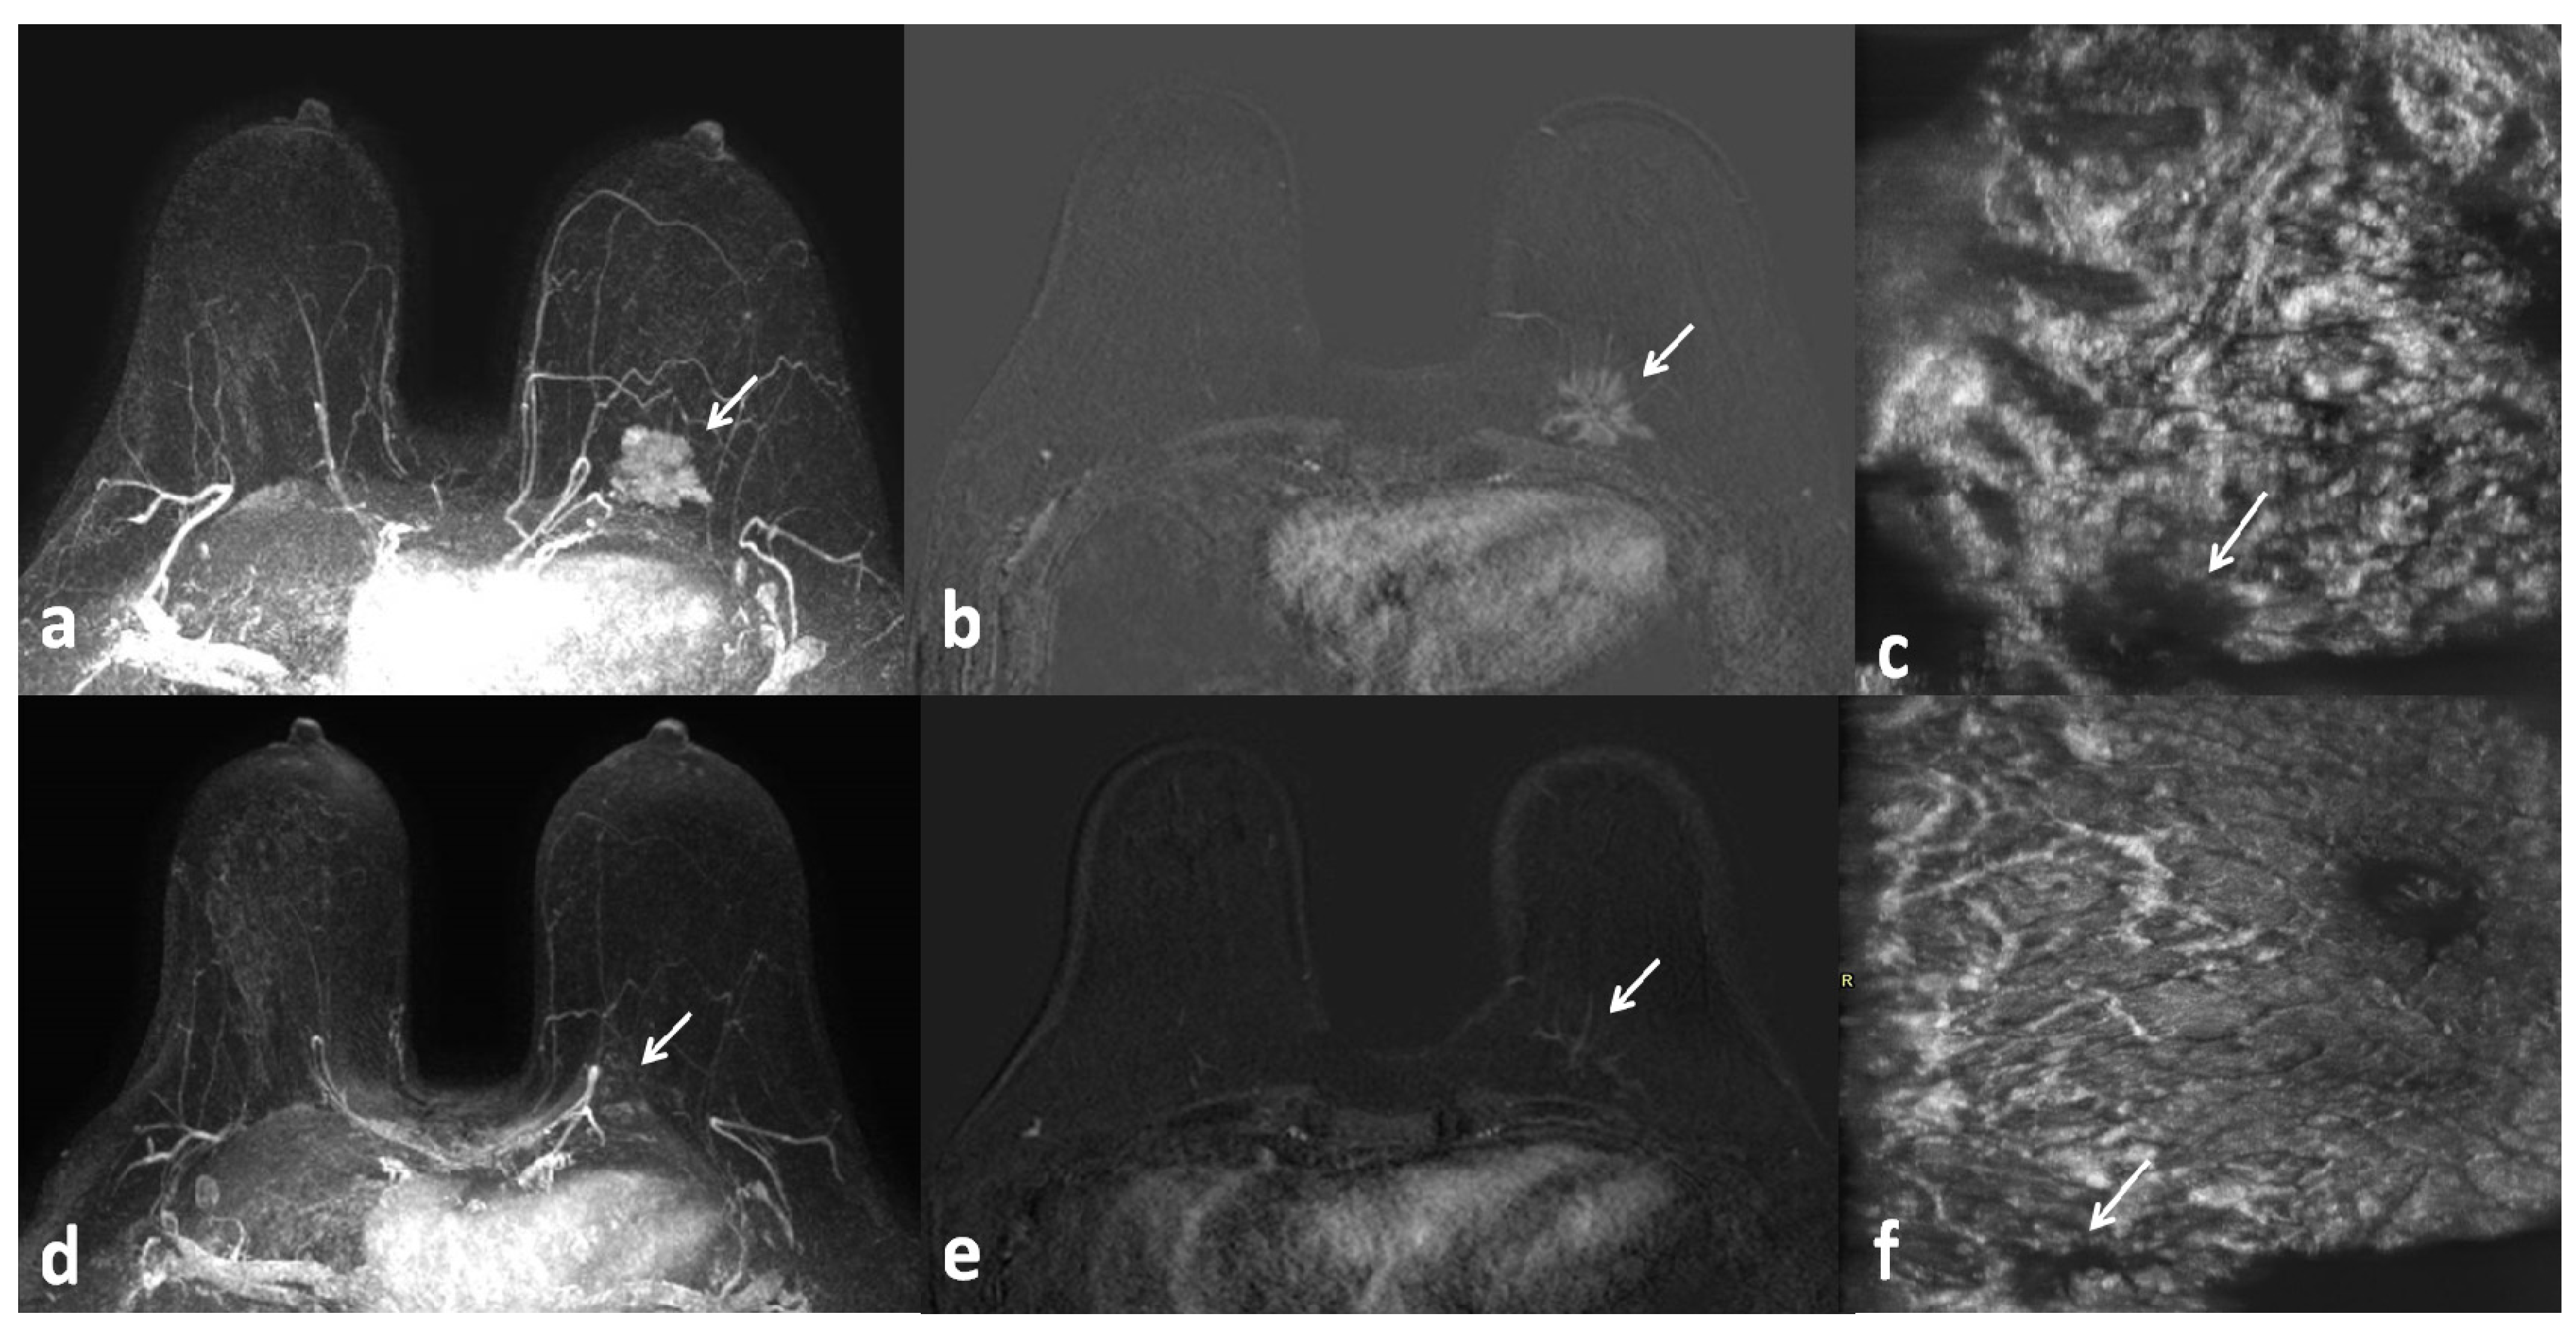

1. Introduction

2. Materials and Methods

2.3. ABUS Technique

2.4. Image Analysis

3. Results

4. Discussion